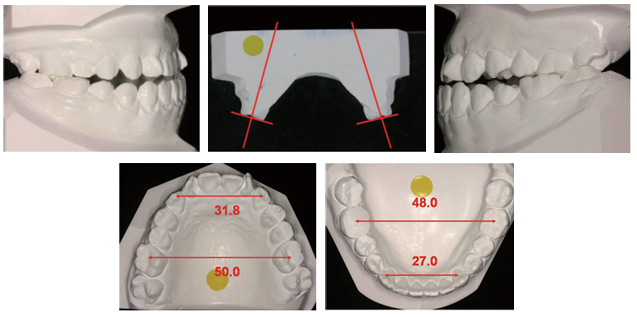

앞니와 마찬가지로 어금니도 위아래가 거꾸로 물리기도 하는데, 이를 진단할 때는 상,악 대구치(큰 어금니)의 위치를 기준으로 합니다. 좌우 양측성으로 어금니가 반대로 물리는 경우는 상,악 대구치가 양측에서 정상 위치보다 설측(혹은 구개측) 즉, 안쪽에 위치함을 의미하고, 반면에 좌우 어느 한쪽이 거꾸로 물린다면 하악 어금니가 어느 한쪽에서 협측(바깥쪽)으로 존재함을 의미합니다. 양측성 반대교합의 원인이 상악의 악,궁 자체가 좁아서 나타나는 골격성인지, 또는 골격의 폭경은 정상이나 치열궁 폭경이 좁아서 나타나는 문제인지 알아야 합니다. 상,악 치열이 위치하는 기저골(뼈)의 폭경은 치아모형에서 악궁의 폭경을 관찰하여 알 수 있으며 CT를 촬영하여 보다 정밀하게 계측할 수 있습니다. 구개의 기저가 넓지만 치조돌기(잇몸뼈)가 안으로 기울었다면 반대교합은 치아에 의한 것(치성)이며 치조골(잇몸뼈)의 변형에 의해 야기된 것입니다. 만약 구개가 좁고 상,악 치아가 밖으로 기울었음에도 불구하고 반.대.교.합이 있다면 문제는 근본적으로 좁은 상악골 폭경에 기인한 골격성인 것입니다. 공간의 전후 및 수직면에서의 골격 변형에 대해 치열의 변화로 인해 보상작용이 일어나는 것과 마찬가지로 치아는 수평적인 골격 문제도 인해 보상이 일어날 수 있는 데 기저골 폭경이 좁으면 협측(바깥)으로, 넓으면 설측(안쪽)으로의 치아 경사 즉, 치아가 쓰러지는 현상이 일어납니다.

치열궁이 좁거나 협착된 환자에서는 미소도 역시 좁게 보일 것이며 심미적으로 덜 매력적입니다. 미소 시에 보이는 협측회랑(buccal corridor)의 크기 즉, 상악 구치(특히 소구치)와 안쪽 볼과의 거리가 크면 좁은 미소를 보여 심미적이지 않다고 여기게 됩니다. 볼 안쪽 공간이 치열궁보다 두드러지게 넓을 때, (미소 시 치열이 적게 보임) 상.악.궁을 넓히는 것이 미소를 개선할 수 있습니다. 반대로 너무 넓은 상.악.궁 또한 비심미적이므로 미소 시 볼과 어금니의 관계는 악궁의 폭경을 평가하는 또 다른 방법입니다. 자연치열의 과도한 확.장은 동일하게 자연스럽지 않은 치아의 모습을 유발할 것이므로 모든 사람에게 횡적인 확.장이 적절한 것은 아닙니다. 이러한 점들을 고려하여 악궁을 넓혀야 하는지 결정하게 되며 어금니가 반대로 물리고 있다면 상악의 악.궁을 넓히게 됩니다.